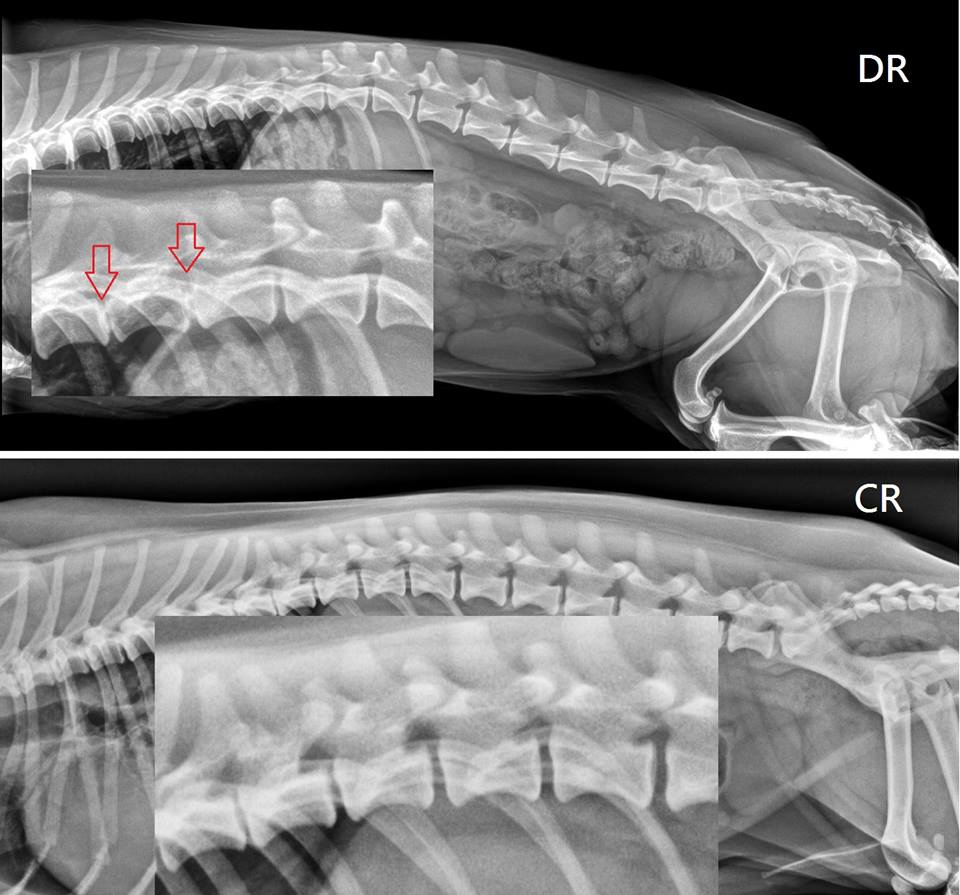

DR VS. CR

時代就像滾輪一樣,推著醫學一直在進步,

以前可能是幾十年一個世代,現在不到幾年的光景,

就完全換了一個世代。